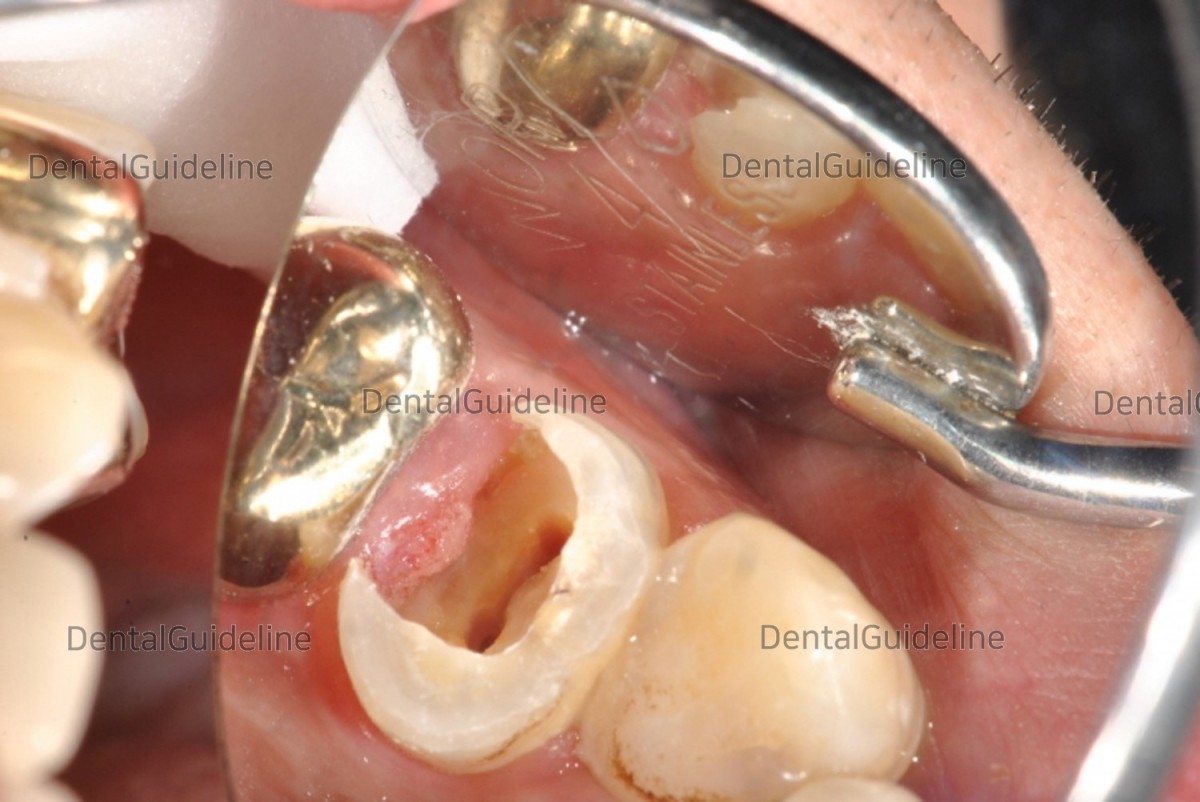

8. Photo of opening the flap and performing crown lengthening surgery.

10. A photo of removing the alveolar bone between the teeth and around the teeth using a piezo surgical machine.